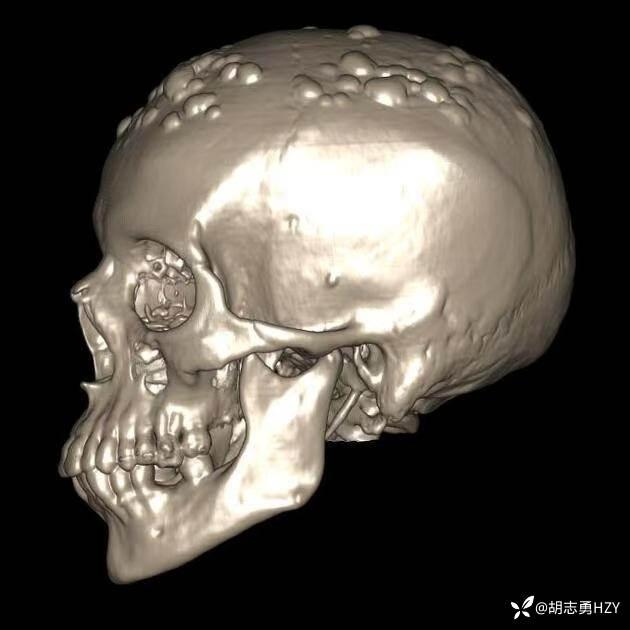

女性,45岁,家族性腺瘤性息肉病,额部顶部多发无痛性硬质包块